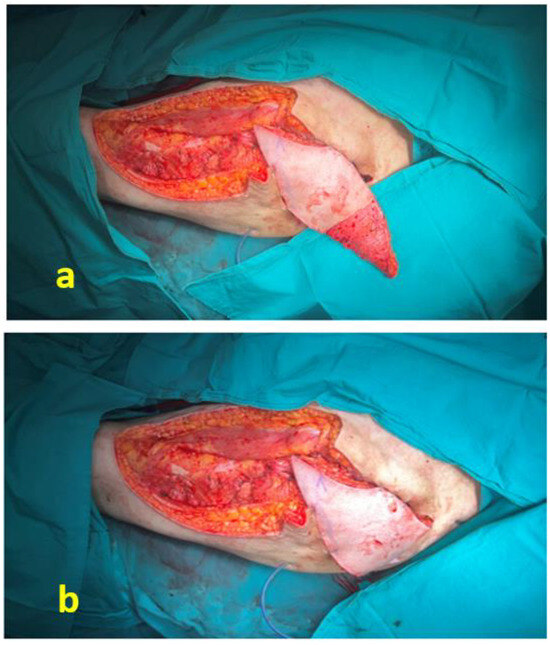

Musculocutaneous Pedicled Anterolateral Thigh Flap for Reconstruction of Stage IV Trochanteric Pressure Ulcers: Experience in Chronic and Acute Compression Injuries

J. Clin. Med. 2026, 15(5), 1988; https://doi.org/10.3390/jcm15051988 - 5 Mar 2026

Background/Objectives: Trochanteric pressure ulcers represent a challenging reconstructive problem due to their depth, frequent infection, and tendency for recurrence. Durable coverage with well-vascularized tissue capable of effective dead-space management is essential for long-term stability. The pedicled musculocutaneous anterolateral thigh (ALT) flap offers substantial [...] Read more.

Background/Objectives: Trochanteric pressure ulcers represent a challenging reconstructive problem due to their depth, frequent infection, and tendency for recurrence. Durable coverage with well-vascularized tissue capable of effective dead-space management is essential for long-term stability. The pedicled musculocutaneous anterolateral thigh (ALT) flap offers substantial soft-tissue volume with reliable regional vascularity. Methods: A retrospective review was performed of consecutive patients with Stage IV trochanteric pressure ulcers who underwent reconstruction using musculocutaneous pedicled island ALT flaps between January 2020 and August 2023. Ulcers were classified according to the European Pressure Ulcer Advisory Panel, National Pressure Injury Advisory Panel, and Pan Pacific Pressure Injury Alliance International Guidelines. Patients with a minimum follow-up of 24 months were included. Demographic characteristics, ulcer etiology, prior flap history, comorbidities, flap dimensions, postoperative complications, and recurrence rates were analyzed. Results: Eight patients (4 males, 4 females; mean age 46.4 years, range 35–63) were included. Six ulcers (75%) were related to prolonged immobilization, and two (25%) developed following entrapment during the 2023 Kahramanmaraş earthquake. All donor sites were closed primarily. Minor recipient-site complications, including seroma and limited suture dehiscence, occurred in two cases. No partial or total flap necrosis was observed. During a mean follow-up of 42.4 months (minimum 24 months), no recurrence occurred. Conclusions: Musculocutaneous pedicled ALT flaps incorporating a substantial portion of the vastus lateralis muscle allowed effective dead-space obliteration and durable soft-tissue coverage in Stage IV trochanteric pressure ulcers. Primary donor-site closure was achievable without major morbidity. These findings support the use of the pedicled ALT flap as a consistent regional option in complex trochanteric defects, including both chronic immobilization-related and acute compression-related cases. Full article

Show Figures

Figure 1